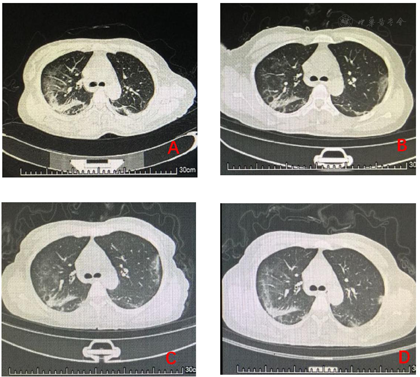

患者女性,44岁,因"反复发热、咳嗽10 d"于2020年1月21日收住重庆三峡中心医院重症肺炎应急病区。患者在武汉市华南海鲜市场附近务工。2020年1月10日,患者出现咳嗽,咳黄色脓痰,同时发热,测体温达39 ℃以上,伴鼻塞、喷嚏、全身疼痛及头昏,无畏寒、寒战,无喘息、气促,无胸痛、胸闷、心悸,无恶心、呕吐、腹痛、腹泻。患者先后在武汉市3处个体诊所就诊,均予以退热等对症治疗(具体用药不详),症状未见缓解。1月15日患者回到重庆市巫山县,直接入住巫山县人民医院。入院时CT提示双肺多发大小不等磨玻璃斑片状影。1月18日复查CT示双肺病灶较入院时明显增加,同日行咽拭子标本采样。1月19日咽拭子标本采样结果为2019新型冠状病毒(2019 novel coronavirus,2019 - nCoV)核酸阳性。住院期间肺炎支原体IgM弱阳性,柯萨奇病毒抗体IgM弱阳性,而EB病毒、腺病毒、A流感病毒及呼吸道合胞病毒抗体IgM均为阴性。给予患者重组人干扰素α-1b雾化及洛匹那韦/利脱那韦(克立芝)口服,同时哌拉西拉舒巴坦及莫西沙星抗感染,患者仍有中度发热,体温在38.5 ℃左右,干咳明显,呼吸困难,经市级专家小组会诊后转入重庆三峡中心医院重症肺炎应急病区继续治疗。患者既往无高血压、糖尿病病史。入院时查体:体温36.8 ℃,脉搏71次/min,呼吸25次/min,血压117/69 mm Hg(1 mm Hg=0.133 kPa)。神清,精神可,全身浅表淋巴结未扪及肿大,皮肤无红疹斑点,结膜无充血,口唇红,咽部无充血,扁桃体不肿大,呼吸节律规整,双肺呼吸音粗糙,未闻及干湿罗音,心音有力,心律齐,各瓣膜区未闻及病理性杂音,腹平软,无压痛及反跳痛,肝脾无肿大,肠鸣音可闻及,双下肢无水肿。入院后相关检查:血气分析(面罩吸氧4 L/min)示pH值7.40,氧分压147 mm Hg,二氧化碳分压45 mm Hg,乳酸1.3 mmol/L;血常规示白细胞计数3.5×109/L,中性粒细胞计数3.17×109/L(90.6%),淋巴细胞计数0.87×109/L(7.8%);肝功能:总蛋白58.9 g/L,清蛋白32.7 g/L,前清蛋白70 mg/L;超敏C反应蛋白58.5 mg/L;降钙素原(PCT)0.05 ng/mL(参考值:PCT<0.046 ng/mL);凝血像示纤维蛋白原8.28 g/L;电解质、肾功能、心肌酶谱、综合6项细胞因子[白细胞介素(IL)-4、IL-6 IL-10、IL-17、肿瘤坏死因子(TNF)-α、γ干扰素(IFN-γ)]、甲状腺功能、糖化血红蛋白均正常,真菌(1,3)-β-D葡聚糖、结核分枝杆菌IgM及IgG抗体均阴性,痰培养及血培养亦为阴性。1月22日胸部CT显示双肺散在斑片状密度增高影及斑片状模糊影,考虑双肺感染性病变,右侧胸腔少量积液(图1A)。1月23日淋巴细胞亚群分析显示淋巴细胞317×106/L,总T淋巴细胞190×106/L(59.99%),辅助/诱导T淋巴细胞(CD4+)106×106/L(33.68%),抑制/细胞毒T淋巴细胞(CD8+)84×106/L(26.6%),CD4+/CD8+比值1.27,总B淋巴细胞71×106/L(22.26%),自然杀伤细胞53×106/L(16.68%)。

A:1月22日;B:1月24日;C:1月26日;D:1月28日

患者入院诊断为NCP重症病例。入院后予以面罩吸氧(3~5 L/min);重组人干扰素α-1b 30 μg雾化抗病毒,每天2次;克立芝(200 mg/50 mg)口服抗病毒,每次2片,每天3次;莫西沙星氯化钠250 mL静脉滴注,每天1次;甲泼尼龙琥珀酸钠40 mg静脉滴注,每天2次;胸腺五肽10 mg肌内注射,每天1次。患者咳嗽、气促等症状逐渐好转。患者血糖高,1月23日停用甲泼尼龙琥珀酸钠血糖恢复正常。1月24日复查胸部CT显示双肺感染性病变,双肺病灶较前1月22日吸收减少(图1B)。1月24日血常规显示白细胞11×109/L,中性粒细胞9.56×109/L(87.2%),淋巴细胞0.87×109/L(7.9%);淋巴细胞亚群分析显示淋巴细胞776×106/L,总T淋巴细胞515×106/L(66.3%),CD4+T细胞323×106/L(41.34%),CD8+ T细胞199×106/L(25.48%),CD4+/CD8+比值1.62,总B淋巴细胞196×106/L(25.48%),自然杀伤细胞51×106/L(6.68%);6项细胞因子各值均正常。1月25日将面罩吸氧改为鼻导管吸氧。1月26日胸部CT显示双肺散在斑片状、片絮状及条絮状影,边缘模糊不清,与1月24日CT片相比,局部实变灶较前稍增多,余较前大致相仿(图1C)。1月27日血常规显示白细胞11.1×109/L,中性粒细胞9.21×109/L(83.4%),淋巴细胞1.24×109/L(11.2%);淋巴细胞亚群分析示淋巴细胞1 005×106/L,总T淋巴细胞702×106/L(69.87%),CD4+T细胞432×106/L(40.52%),CD8+T细胞317×106/L(29.74%),CD4+/CD8+比值1.36,总B淋巴细胞169×106/L(17.96%),自然杀伤细胞107×106/L(11.32%);综合6项细胞因子、血清超敏C反应蛋白及PCT均正常。1月28日胸部CT与1月24日比较无明显变化(图1D)。随着病情的好转,各种细胞呈均衡性的恢复,见图2。患者1月26日、28日两次连续2次咽拭子采样提示2019 -nCoV核酸阴性,体温正常7 d,无咳嗽、气促,患者达到解除隔离和出院标准,于1月29日予以出院。